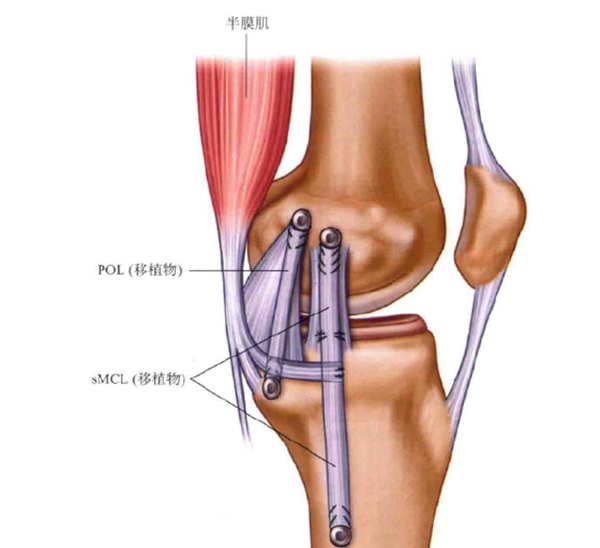

膝关节内侧副韧带(MCL)损伤是膝关节最常见的损伤之一,绝大多数MCL损伤不需要手术治疗,内侧副韧带浅层(sMCL)、后内侧关节囊(PMC)、后斜韧带(POL)对维持膝关节外翻和旋转稳定发挥着不同的作用。直接的外翻应力伴有胫骨外旋是导致MCL损伤的最主要因素。

图 1黑色箭头为内侧副韧带深层,红色剪头为内侧副韧带浅层